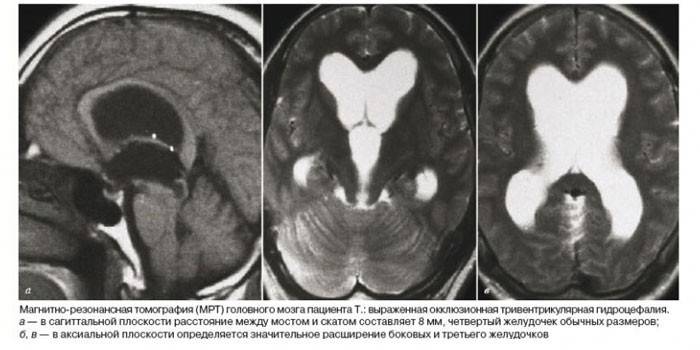

Un neurólogo puede detectar hidrocefalia en el primer examen del paciente. Para determinar el tipo y el grado de la enfermedad, se realizan exámenes adicionales: ultrasonido, resonancia magnética, radiografía del cráneo.